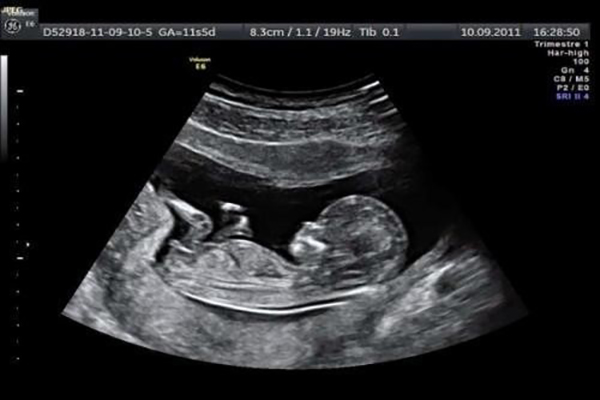

Hình thức đầu tiên mà các mẹ có thể thực hiện đó chính là siêu âm. Với hình thức này các bác sĩ siêu âm với kinh nghiệm và chuyên môn của mình sẽ nhìn rõ được bộ phận sinh dục của thai nhi. Tuy nhiên, có một điều các cha mẹ nên biết. Thường vào khoảng tuần thứ 12 bộ phận sinh dục của bé đã hình thành và thời điểm này khi siêu âm sẽ nhìn ra được thai nhi là trai hay gái. Tuy nhiên, thời điểm này cũng rất mờ. Nếu bác sĩ tay nghề chưa cao thì có thể nhìn chưa rõ và dẫn đến phán đoán sai lầm. Để biết chính xác nhất thì từ tuần 14 trở đi các bác sĩ sẽ nhìn thấy rõ ràng bộ phận sinh dục của thai nhi.

Khi chị em thực hiện siêu âm thì lúc này hình ảnh thai nhi sẽ được các bác sĩ phóng to. Sau khi đo các thông số cơ thể chiều dài của thai nhi thì đo độ mờ da gáy với da của bé là màu trắng và khoảng mờ đó chính là màu đen. Trường hợp các mẹ đo độ mờ da gáy của thai nhi ở tuần thứ 11 nếu chúng là khoảng 2mm thì mẹ an tâm. Còn nếu ở tuần 13 thì độ mờ da gáy đạt tiêu chuẩn là 2,8mm còn ở tuần tiếp theo thì chúng sẽ lớn hơn 3mm.